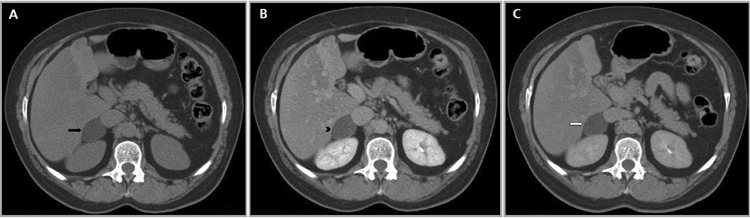

Los valores más utilizados son un 40% de lavado relativo de en fase tardía realizada a los 15 minutos y un lavado absoluto de 60%. De este modo cualquier lesión que muestre un lavado relativo mayor al 40% o absoluto mayor al 60% es consistente con un adenoma, con una sensibilidad y especificidad cercana al 100% (Figura 14 a, b y c). Dado la rapidez con que se obtiene un TAC de abdomen en la actualidad, algunos trabajos han recomendado utilizar cortes tardíos realizados a los 10 minutos, con el fin de optimizar el tiempo de examen, y utilizar un valor relativo de corte más conservador del 50%9.

A

B

C Figura 14. Tomografía computada de un adenoma suprarrenal izquierdo típico. Se ha colocado un circulo que representa la región de interés en la lesión de la glándula suprarrenal izquierda, obteniendo una medición promedio (Avg) expresada en unidades Hounsfield (UH). En fase precontraste (a) su densidad es de 0 UH, (flecha), en fase protovenosa (b) alcanza una densidad de 59 UH (cabeza de flecha), y en fase tardía (c) su lavado es de aproximadamente un 50%, llegando a una densidad de 30 UH.